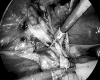

Figure 7.

Dissection of sac after creation of peritoneal flap.